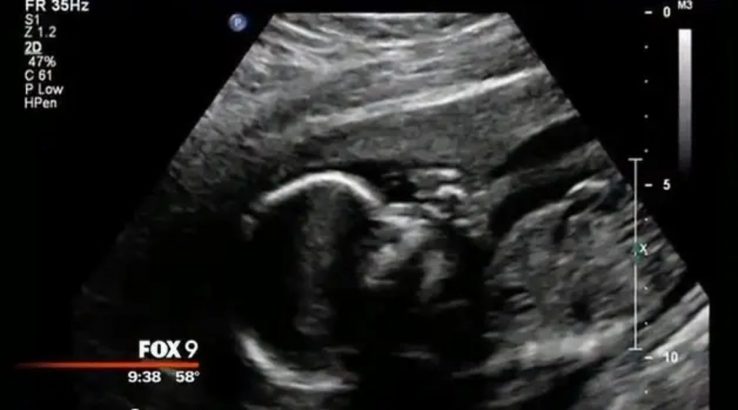

Валері, мати з Міннесоти, з нетерпінням чекала народження свого сина Ноя. Але безпосередньо перед пологами її світ перевернувся з ніг на голову. Син, якого вона носила дев’ять місяців, більше не рухався.

Лікар підтвердив найгіршу новину: її дитина померла ще до народження. Валері була спустошена, а кімната Ноя залишалася недоторканою понад рік, болісним нагадуванням про цю втрату.